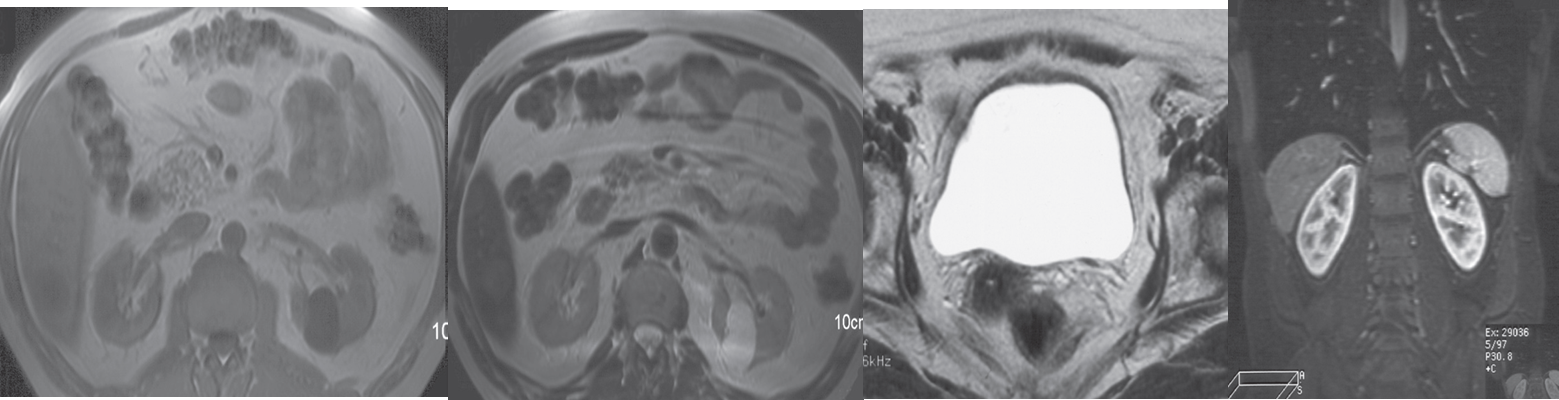

MRI gives similar anatomical information to CT, with the advantage of being able to obtain scans directly in multiple planes.

It is generally used in selected circumstances, e.g.:

- = To demonstrate renal artery stenosis or inferior vena caval extension of renal tumours,

- = To clarify problems not solved by ultrasound or CT.

- = To assess the extent of bladder or prostate cancer prior to consideration for surgery

Calcification is not visible on MRI, which is one of the main disadvantages of the technique for renal tract imaging.